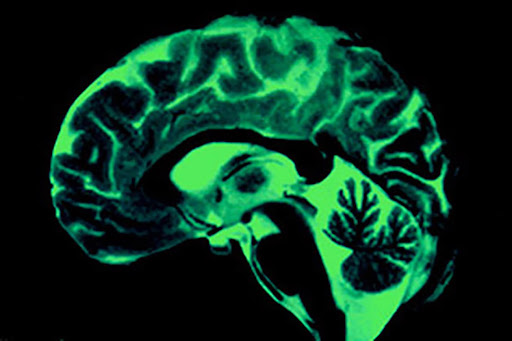

Fear And The Brain

Fear Starts In The Brain And The Physical Effects Throughout Our Body Help Us Adjust.

Fear weakens our immune system and can cause cardiovascular damage, gastrointestinal problems such as. Web in more dire circumstances, however, the brain’s fear response can be critical for survival. While the brain does the brunt of the processing and coordination work, the entire body quickly gets involved to create the fear response.